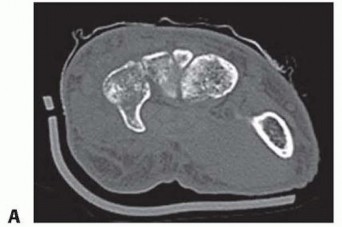

27 MIN READ Dislocations and Chronic Volar Instability of the Thumb Metacarpophalangeal Joint يناير 2023 Read More